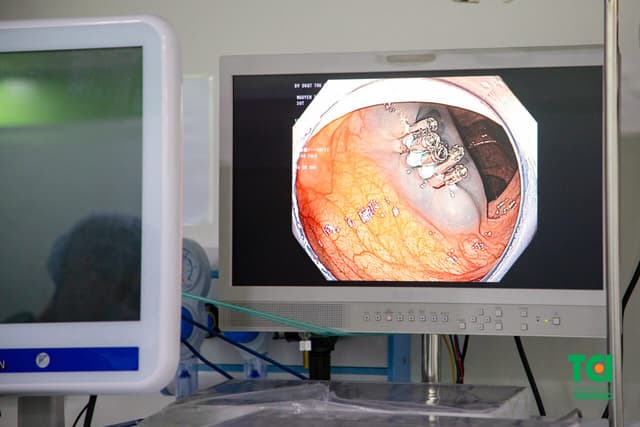

Khi được phát hiện có nhiều polyp đại tràng cùng lúc, người bệnh thường mang tâm lý hoang mang và lo ngại về việc tiến hành điều trị tốt nhất. Hiện nay, cắt polyp qua nội soi là chỉ định tối ưu được thực hiện. 1. Chẩn đoán polyp đại tràng 1.1. Polyp đại tràng […]

Bị polyp đại tràng rất phổ biến đặc biệt là ở người lớn tuổi khi tỷ lệ mắc bệnh chiếm tới 30-50%. Polyp đa phần là lành tính nhưng vẫn có nguy cơ cao phát triển thành ác tính về sau. Vì vậy cắt bỏ polyp là yêu cầu cần thực hiện để phòng chống […]